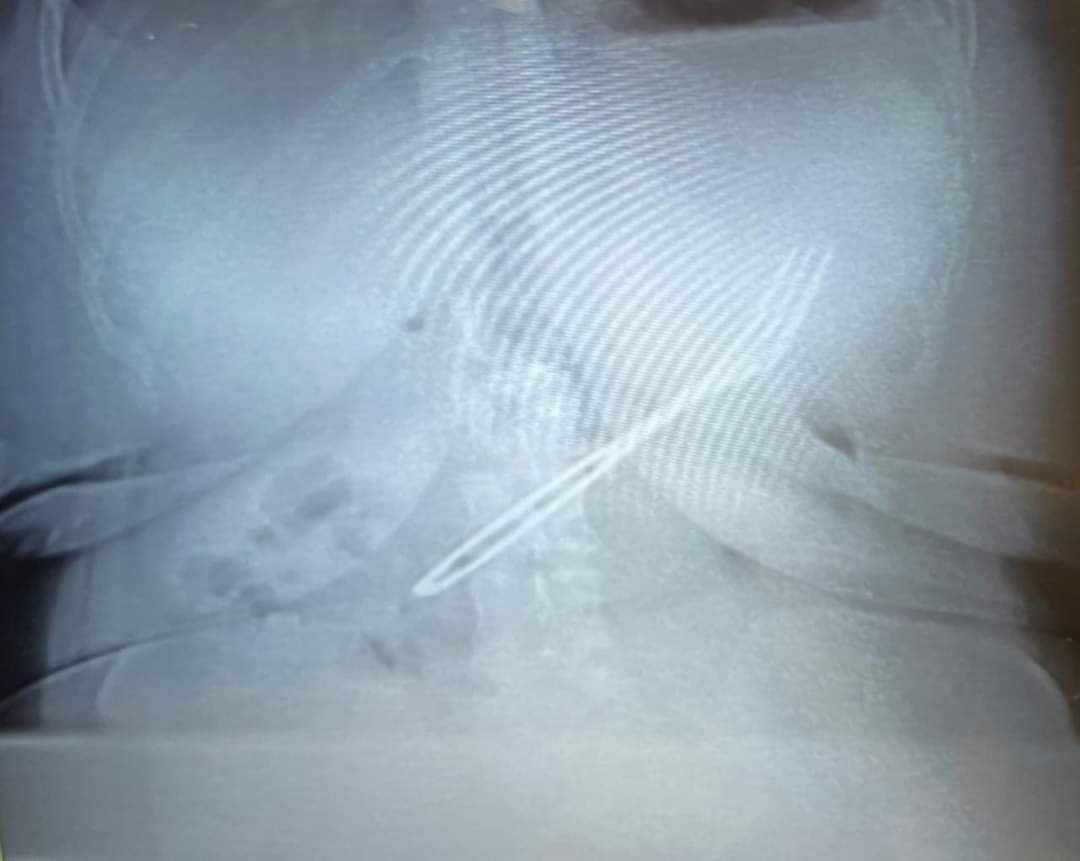

وأضاف غنيم انه تم عمل اشعة عادية على البطن والحوض وضحت وجود الجسم الغريب مستقر داخل تجويف المعدة، وتم تشكيل الفريق الطبي وبدء تجهيز الحالة لعمل منظار على المعدة وتبليغ فريق التخدير فورا لبدء التحضير لتخدير المريضة كليا وتم دخول المريضة لوحدة مناظير الجهاز الهضمي بقسم الأمراض الباطنة بمستشفى الجراحات الجديد لعمل منظار علوي على الجهاز الهضمي بالمجان.

وأفاد عميد كلية الطب بجامعـة طنطـا عن نجاح فريق طبي مشكل من وحدة مناظير الجهاز الهضمي بقسم الأمراض الباطنة وقسمي الأنف والأذن والحنجرة والتخدير والعناية المركزة الجراحية في استخراج شوكة طعام معدنية ذات يد خشبية بأسنان مدببة بالمنظار من تجويف معدة مريضة تبلغ من العمر ٣٥ عاما وذلك بمستشفى الجراحات الجديد بمستشفيات جامعـة طنطـا.

وأكد الدكتور أحمد غنيم عميد الكلية ورئيس مجلس إدارة المستشفيات الجامعية أن هذا المنظار يعد من الحالات الصعبة والمعقدة نظرا لطول الشوكة المعدنية الذى تم قياسها بعد استخراجها من تجويف معدة المريضة " ٢٠ سم " ووجود يد خشبية للشوكة وكذلك أسنانها المدببة كنتيجة لتعاون مثمر بين أقسام الكلية وعن تفاصيل استخراج الشوكة أوضح سيادته أنه تم تخدير المريضة كليا من خلال أطباء قسم التخدير واستخراج الشوكة في زمن قياسي ٢٥ دقيقة فقط باستخدام "جفت " مخصص في إخراج الأجسام الغريبة بطريقة رأسية دون تجريح المعدة أو المريء بالمرور من المعدة إلى المريء بسلام ومنه إلى البلعوم بمشاركة طبيب الأنف والأذن والحنجرة وخرجت الحالة بسلام من المستشفى،